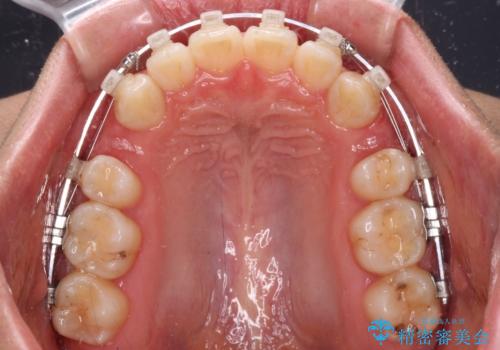

- 矯正装置

- クリアブラケット

- 上の前歯が下唇に引っかかる感じが気にして来院された患者様です。

上下歯列の前後位置を見ると、上顎が全体的に前方に位置しており、上顎前歯が前方に突出しているものの、横顔の印象はそれほど口元が突出しているものではない状態でした。

口元を極端に引っ込めた印象にしないため、上顎は左右第一小臼歯2本を、下顎は左右第二小臼歯2本を抜歯し、ワイヤー装置にて矯正治療を行うこととしました。